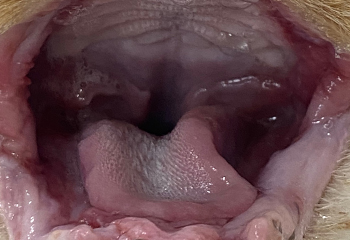

구내염 치료 사례

치료 전

치료 전

치료 전

치료 후(앞니 후방 전발치)

치료 후(전방/후방 전발치)

치료 후(후방 전발치)